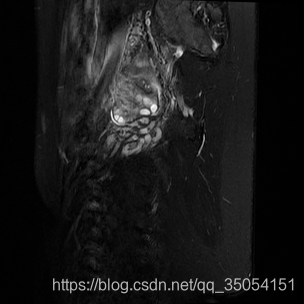

第二种,先把16位的图像归一化,然后*255转成8位,这一种类最为常用,而且可视化效果好,推荐该方法;

一张16位图片保存为8位如下,(切记如果用opencv读取16位,flag字段为cv2.IMREAD_ANYDEPTH)

可以显示